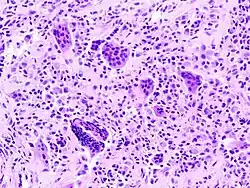

Sinovite vilonodular pigmentada é uma condição benigna e rara que afeta as articulações e tendões. Aproximadamente 75% dos casos envolvem os joelhos. Os sintomas, como por exemplo dor, são sentidos na área afetada.[1]